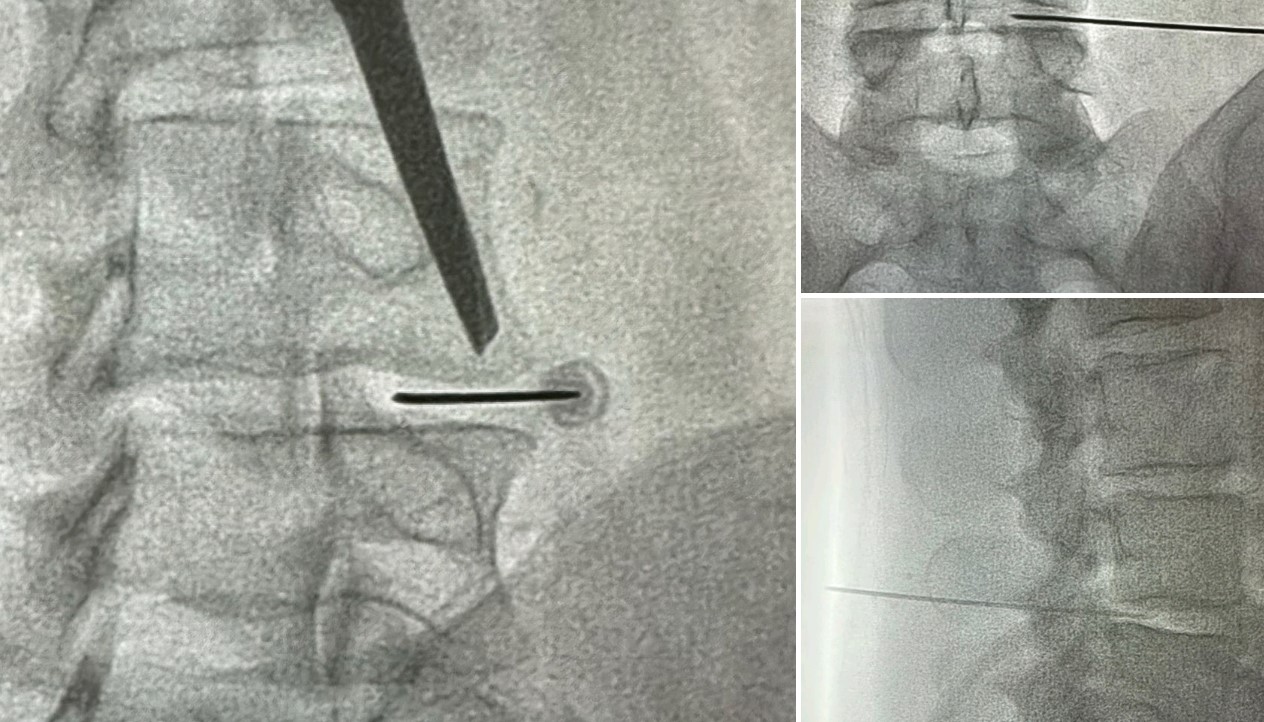

Με τον ασθενή σε πρηνή θέση, υπό τοπική αναισθησία ή μέθη και κάτω από συνεχή ακτινοσκοπική καθοδήγηση, εισάγεται μια ειδική βελόνα σε έναν ή περισσότερους δίσκους στην οσφύ. Στη συνέχεια, γίνεται έγχυση μικρής ποσότητα σκιαγραφικής ουσίας σε κάθε δίσκο για την απεικόνιση αυτού.. Η σκιαγραφική ουσία θα αυξήσει την ενδοδισκική πίεση, γεγονός που μπορεί να εκλύσει πόνο, ο οποίος είναι ενδεικτικός του πάσχοντα δίσκου. Η ακτινοσκοπική απεικόνιση των δίσκων θα βοηθήσει να εξαχθούν τα απαιτούμενα συμπεράσματα και να εντοπισθεί η πηγή του πόνου. Όταν η έγχυση γίνεται σε έναν φυσιολογικό δίσκο, ο ασθενής νιώθει μια ελαφρά πίεση. Όταν, αντίθετα, εισέρχεται σκιαγραφική ουσία σε μη φυσιολογικό δίσκο, ο ασθενής νιώθει έντονο πόνο.